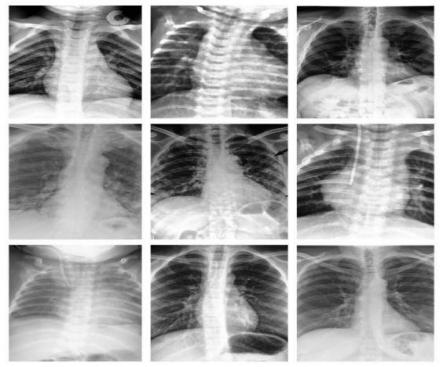

The dataset is divided into two main directories: train and test, with three subdirectories for each category: Normal, Pneumonia, and Lung Tumor. These subdirectories store CT scans for training, validation, and testing. LabelEncoder is used to integer-code the text labels, and the test set is randomly shuffled. The training set contains 80% of the original data, while the validation set holds 20%. A class called Pipeline is defined to efficiently load and preprocess the data. The transforms module is used for image preprocessing to fit the pre-trained MobileNetV2 model, and two data loaders are created for training and validation.

/word/media/image3.jpeg

Figure 2: Part of the pneumonia CT scan images in the dataset